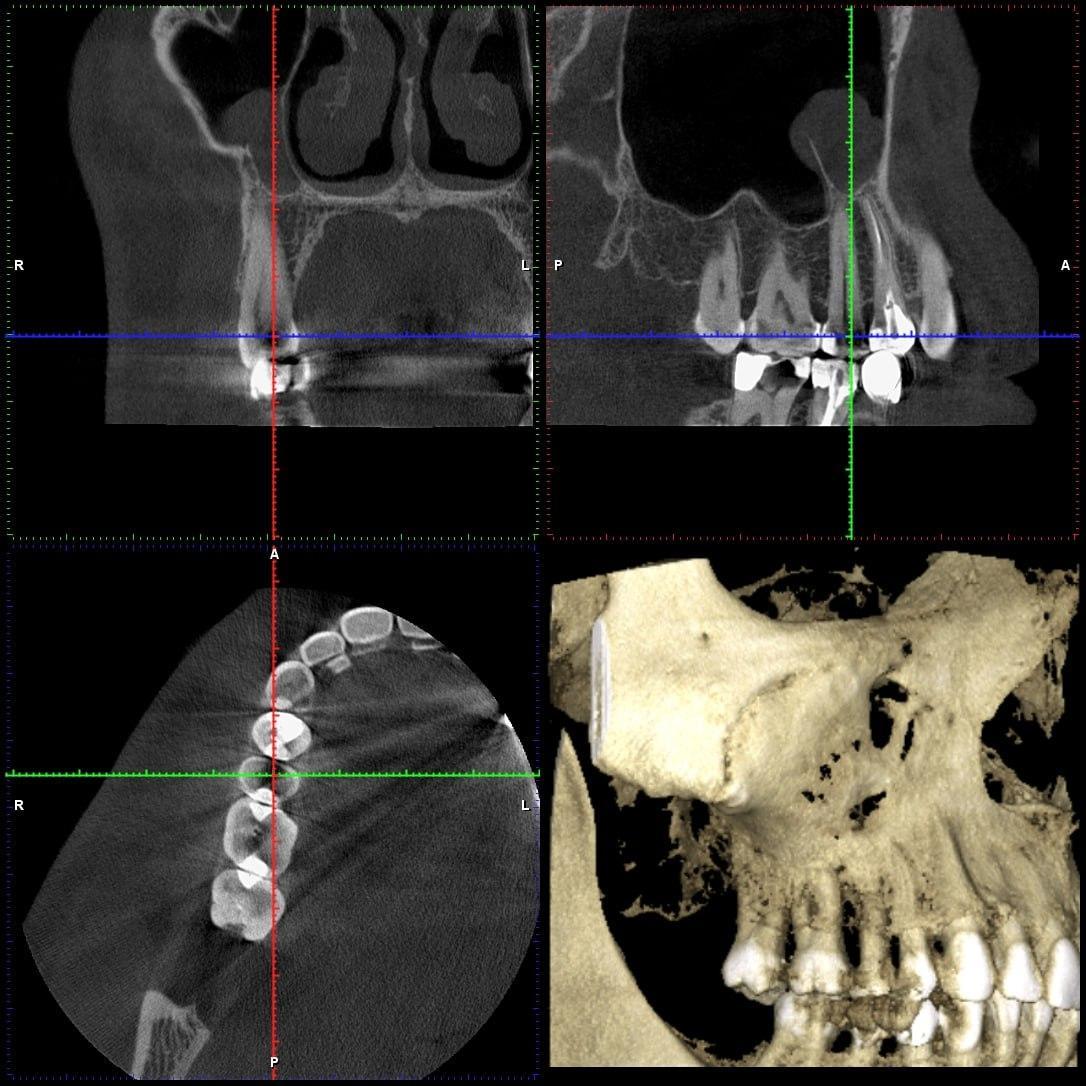

Речь о 15 зубе, и его влиянием на пазуху. Субъективно проблемы начались год назад, после сделанной пломбы на этот зуб. На клкт за пломбой необычная область низкой плотности

Добрый день, скорее всего утолщение слизистой в пазухе является следствием воспаления вокруг верхушки корня 14,а не 15! Думаю,что 14 надо перелечить.

SGanem, обычный плоский прицельный рентген - снимок не показывает проблем. А выкладывал срез из клкт с прицельным фокусом на 14-15 + пазуха.

Участок низкой плотности находится (если это он) в плоскости перпендикулярной лучу обычного снимка, поэтому его прикрывают плотные ткани зуба (дентин тп)